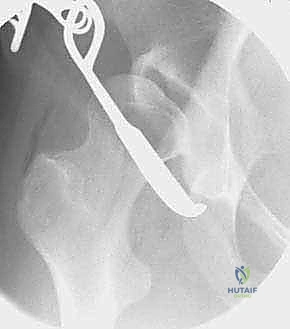

Advanced Imaging and Radiographic Templating

The blueprint for a successful PAO is drawn long before the patient enters the operating suite. Our preoperative imaging protocol is exhaustive. Standard radiography must include a weight-bearing anteroposterior (AP) view of the pelvis to assess the Lateral Center-Edge Angle of Wiberg (normal > 25°), the Tönnis Acetabular Roof Angle (normal 0-10°), and the presence of a crossover sign indicative of cranial retroversion. A False Profile view of the affected hip is mandatory to evaluate the Anterior Center-Edge Angle of Lequesne and de Seze (normal > 20°), quantifying the degree of anterior uncoverage.

Furthermore, we routinely obtain AP views in maximal abduction and internal rotation (the von Rosen view). This dynamic assessment is paramount; it evaluates joint congruency and helps us visualize the potential spherical appearance of the hip after acetabular reorientation. Importantly, it helps identify "hinge abduction," a phenomenon where the laterally subluxated femoral head hinges on the lateral acetabular rim rather than reducing into the true acetabulum. The presence of true hinge abduction is a strong relative contraindication to a standard PAO, often necessitating a concurrent proximal femoral valgus-producing osteotomy or steering the surgeon toward salvage procedures.

Intraoperative fluoroscopy is absolutely critical at this juncture. AP, false profile, and ilio-oblique views are obtained to confirm the correction of the LCEA, normalization of the Tönnis angle, and restoration of anterior coverage without inducing iatrogenic retroversion or femoroacetabular

Clinical & Radiographic Imaging Archive